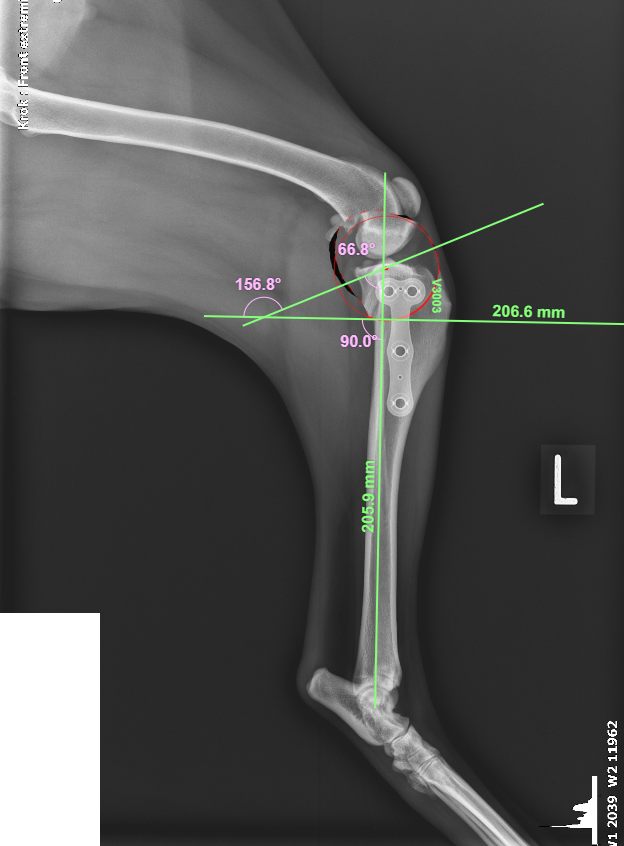

Předtím než provedeme operaci, spočítáme velikost TPA a velikost rotace, kterou potřebujeme dosáhnout k snížení TPA na přibližných 5°.

Obrázek: 19 Vyměření sklonu TPA, obrázek vlastní